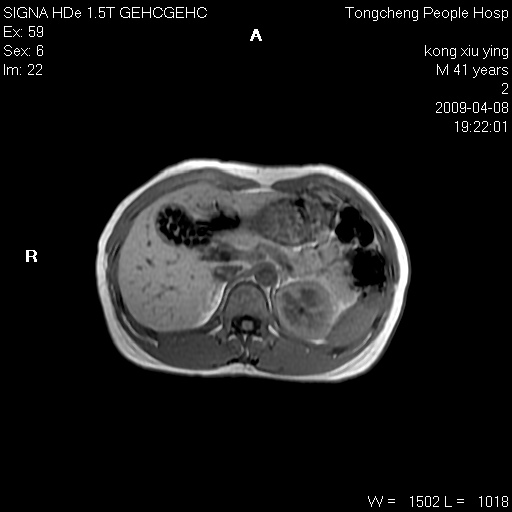

标题: CL1008:【经典】胆囊石榴籽样结石。 [打印本页]

标题: CL1008:【经典】胆囊石榴籽样结石。

女,41岁。健康体检——彩超提示:胆囊显示不清。平素健康,无不适感。

腹部mr扫描及mrcp,图像如下:

胆囊石榴籽样结石。